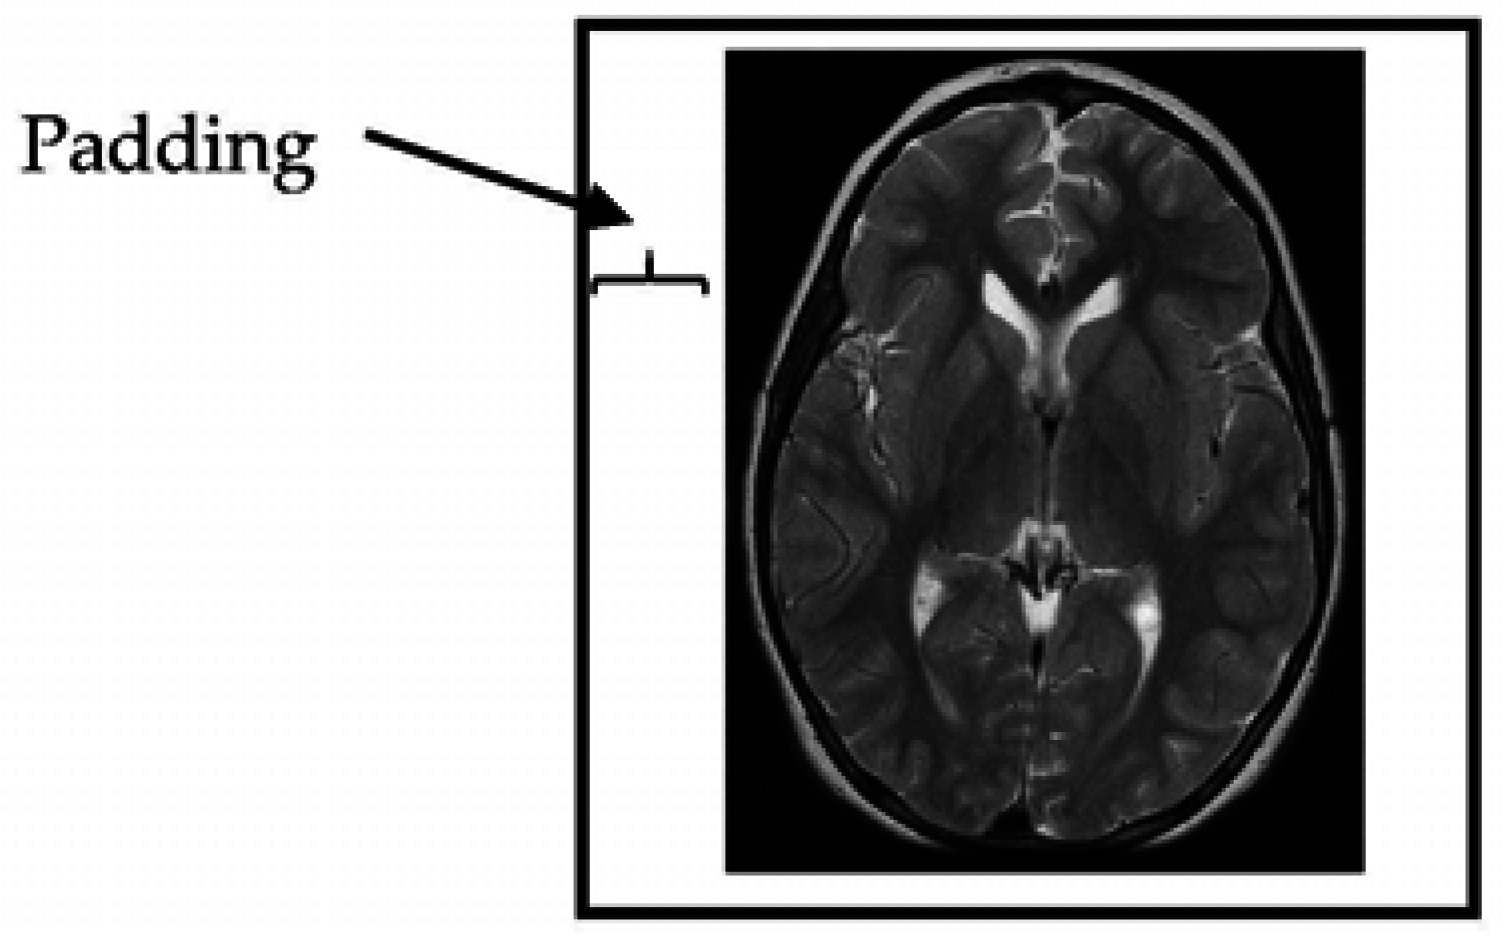

The provided MRI brain slices were collected from two scanners with different spatial resolutions. To enable the use of the full set without bias, the MRI scans were resized to 512 × 512 pixels. All algorithms developed in this study were implemented on squared slices. When the dimensions of the given MRI slices were changed to a square ratio, care was taken to maintain the ratio of voxels to pixels (e.g., pixel spacing). The MRI slices were then resized by adding additional columns from the left and right and additional rows from the top and bottom portions of the MRI slice until the slice size became 512 × 512 pixels in resolution (Figure 2).

Figure 2. Padding of MRI brain image margins by zeros.